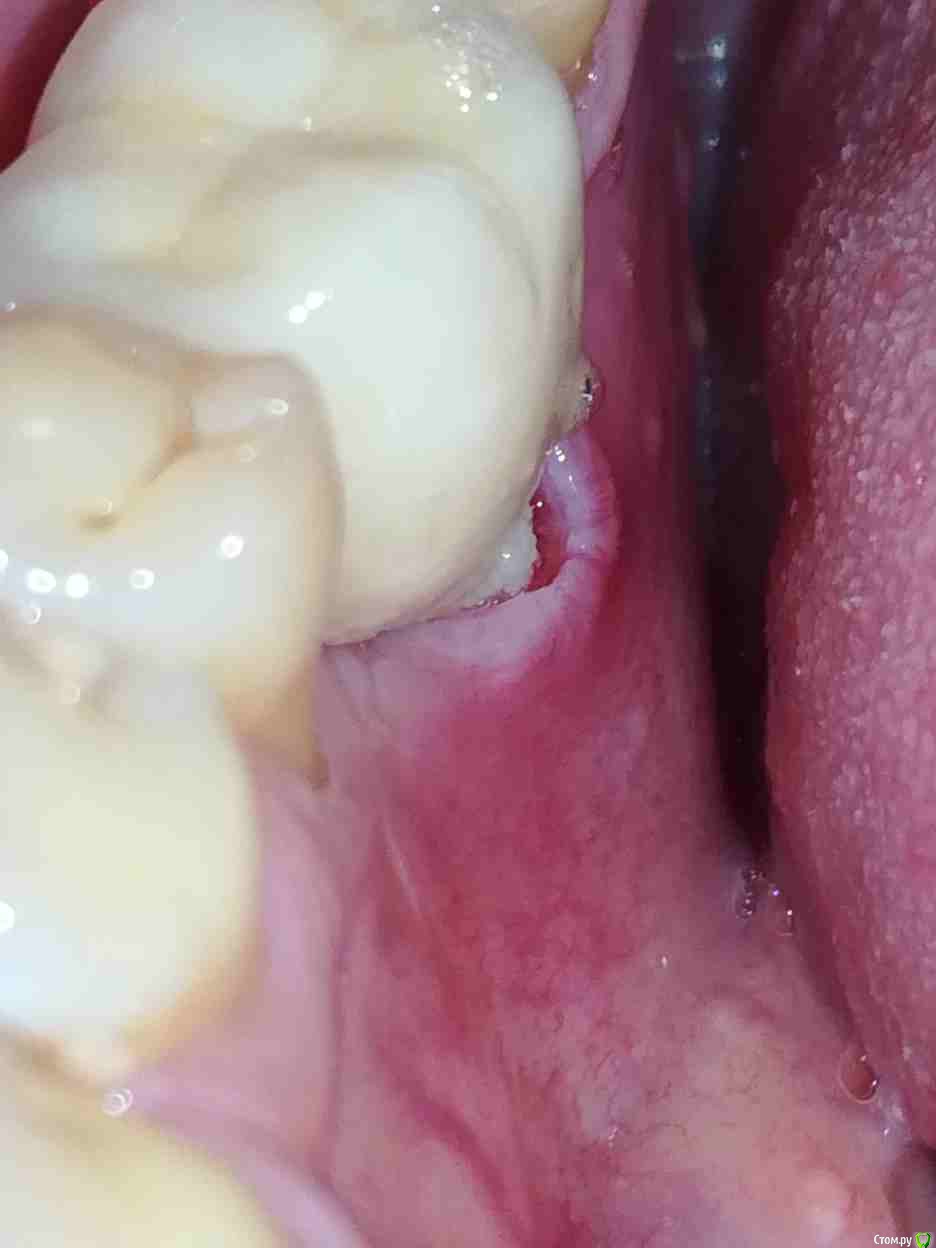

Alex19_73 Опубликовано 3 апреля, 2017 Автор Поделиться Опубликовано 3 апреля, 2017 Первую пластику десны сделали, фото ниже, на днях намечена вторая операция пластики десны.Но обнаружилась проблема в том месте в котором подозревал ее изначально. В четверг начал разглядывать десну со стороны языка и показалось подозрительным что ее край слишком светлый. Разглядел что в районе края десны на коронке какая то неоднородность, ощущение что она трет по десне и похоже десна уже несколько опустилась и вдобавок там не заживающая рана. Фото с кровью было сделано утром до чистки зубов, хотел сделать фотографию, но мешали пузырьки слюны, провел по десне языком и пошла кровь.Врачу еще об этом не говорил. Помогите пожалуйста определиться с тем что делать в такой ситуации, что просить у врача, что должен сделать врач. Коронка несъемная. Ее можно только распилить. Ссылка на комментарий

AndyAndy Опубликовано 3 апреля, 2017 Поделиться Опубликовано 3 апреля, 2017 Ну, по-хорошему коронку надо бы снять. Привести в порядок десну (купировать воспаление, сделать пластику), поставить формирователь на время. Коронку можно попробовать пропилить по месту выхода шахты винта и снять вместе с абатментом, это чтобы не распиливать её Ссылка на комментарий

Alex19_73 Опубликовано 4 апреля, 2017 Автор Поделиться Опубликовано 4 апреля, 2017 Руководитель клиники-очень ответственный и хороший человек, грамотный врач, предложил все то же самое, коронку уже сняли, на очереди пластика и новая коронка, все по гарантии.Считаю что повезло с клиникой. 3 Ссылка на комментарий